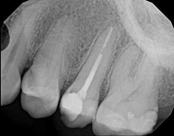

Non-surgical root canal treatment:

6-month follow-upThe patient presented with mild pain, a cavity, and a broken filling was evident. After performing diagnostic testing, the diagnosis was: irreversible pulpitis, symptomatic periradicular periodontitis. Root canal therapy was done and the tooth healed well and is still functioning.